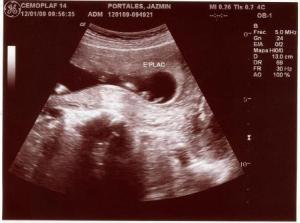

Fotos del 22 Dc 2008:

Informe:

Embrión correspondiente a 9 s cumplidas de embarazo y con FC (frecuencia cardiaca, supongo) de 162 LPM.

Saco gestacional bien conformado y localizado en fondo uterino.

Estructura uniforme de útero con cuello cerrado, ausencia de signos de sangrado gestacional.